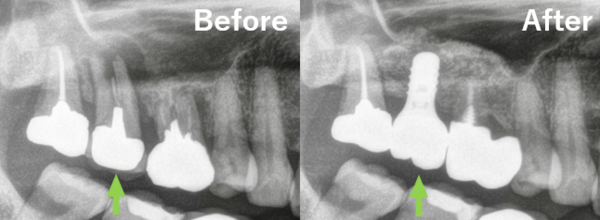

サイナスリフトを行った後、約6ヶ月ほど待ち、再度CTで骨の状態を確認したところ、十分な骨形成が認められました。

その後インプラント埋入手術を行い、手術後はインプラントが骨と結合するまで4ヶ月ほど待ち、上部構造(被せ物)を装着しました。